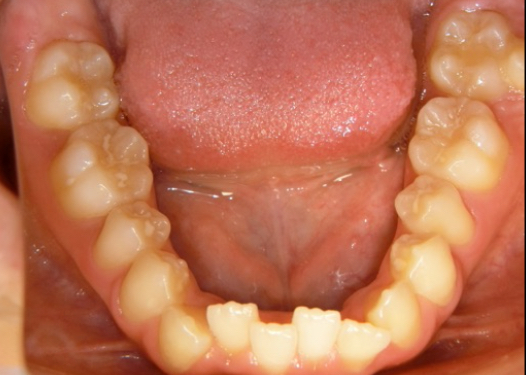

ワイヤー矯正の症例

| 主 訴 | 全体の歯並びをしっかり整えて、バランスの良い噛み合わせにしたい。 |

| 治療詳細 | ワイヤー矯正を使って歯並び全体を整えていきます。歯の重なりやねじれなどを少しずつ改善し、しっかり噛める状態を目指します。治療の進み具合に合わせて細かな調整を行い、きれいな歯並びをつくっていきます。現在はリテーナーで後戻りを防ぎながら安定した状態を保っています。 |

| 治療期間 | 動的期間 1年10ヵ月 保定期間 2年 5ヵ月 |

| 治療費 | 770,000円 |

| リスク・副作用 | ・歯の動き方には個人差があるため、予想された治療期間より延長する場合があります。 |